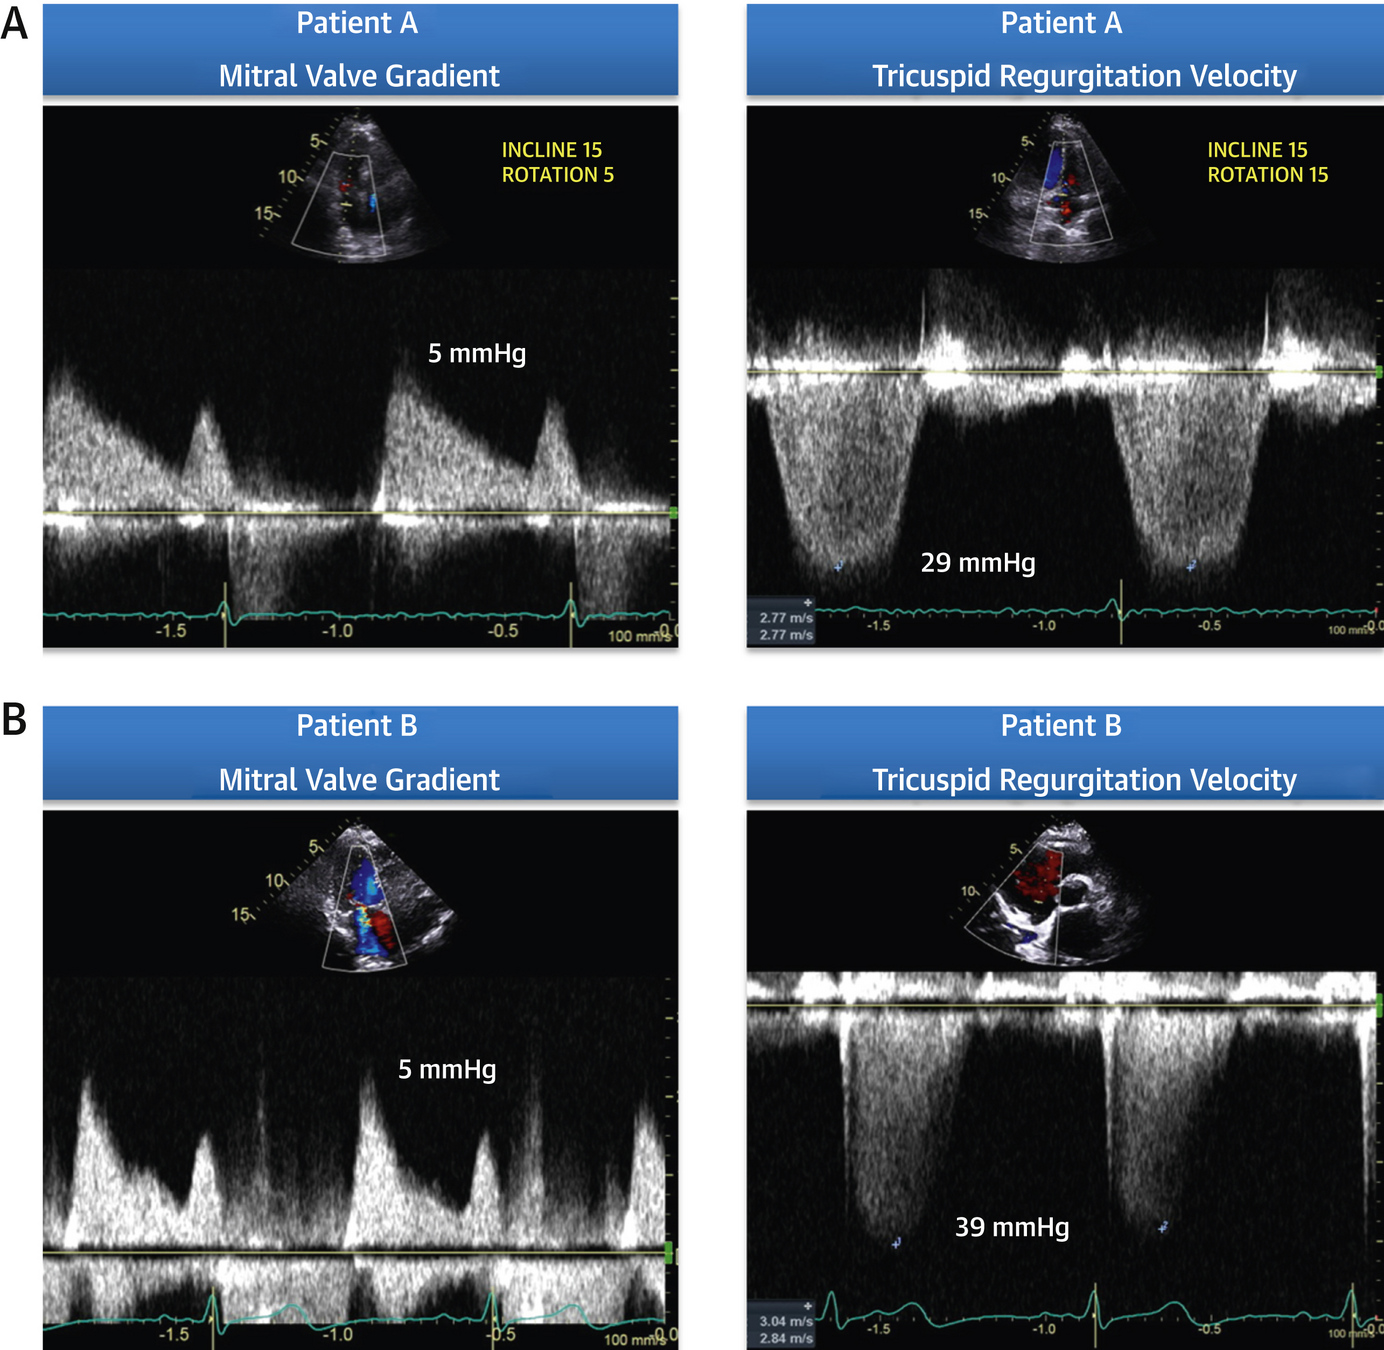

Step D: CFVR

• Assessment: Coronary flow velocity reserve of mid-distal LAD

• Positivity: CFVR < 2

• Success rate of 88% in obtaining CFVR on LAD (3000/3410)

• 80% with exercise (bike) and 81% with dobutamine

•  Acquisition and Interpretation in < 4 minutes

• Assesses both epicardial CAD and coronary microcirculation

• Dopplers obtained and reviewed offline

• *Note: Stress Echo 2030 protocol, pharm SE or if exercise, then given adenosine bolus at end of recovery to assess CFVR

• Acquisition: modified low parasternal and apical views

• Studies agree, onerous, but with training it is possible

• Angina

• No WMA

• CFVR < 2

• Dx:  chronic microvascular dysfunction